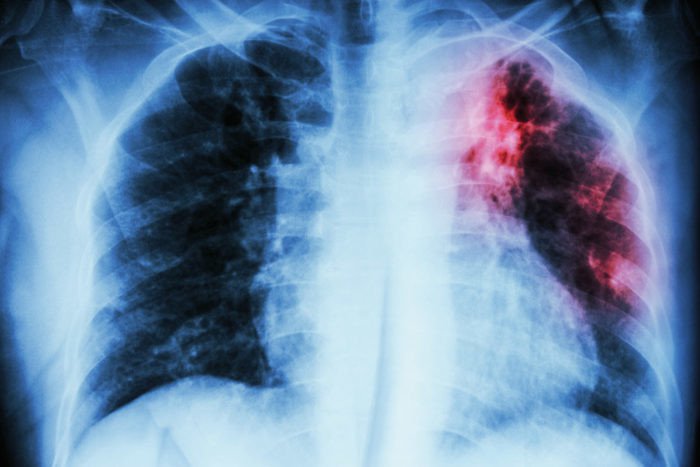

Xơ phổi hay xơ hóa phổi (Pulmonary Fibrosis) là tình trạng các mô trong phổi bị tổn thương, dày lên, xơ cứng, mất chức năng đàn hồi và tạo thành sẹo ở phổi (bao gồm cả đỉnh và thùy phổi). Những vết sẹo ở phổi ngăn chặn và cản trở hoạt động hít thở của người bệnh, khiến người bệnh khó thở cùng các biến chứng nguy hiểm khác.

Ở những người có phổi bị xơ hóa, phế nang bị tổn thương và thành sẹo làm cho mô kẽ cứng và dày lên, kém linh hoạt và có cấu tạo như miếng bọt biển khô cứng, khiến cho người bệnh thở khó khăn hơn. Có rất nhiều nguyên nhân dẫn đến tổn thương phổi gây xơ hóa phổi, một số nguyên nhân thường gặp là: